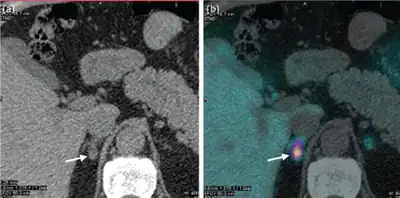

If primary hyperaldosteronism is confirmed biochemically, CT scanning or other cross-sectional imaging can confirm the presence of an adrenal abnormality, possibly an adrenal cortical adenoma (aldosteronoma), adrenal carcinoma, bilateral adrenal hyperplasia, or other less common changes. Imaging findings may ultimately lead to other necessary diagnostic studies, such as adrenal venous sampling, to clarify the cause. It is not uncommon for adults to have bilateral sources of aldosterone hypersecretion in the presence of a nonfunctioning adrenal cortical adenoma, making adrenal venous sampling mandatory in cases where surgery is being considered.[19]